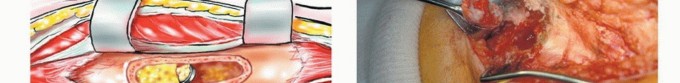

الجراحة هي حجر الزاوية في علاج معظم أورام الشظية، سواء كانت حميدة عدوانية أو خبيثة. يبرع الأستاذ الدكتور محمد هطيف في تقنيات الحفاظ على الطرف، والتي تهدف إلى إزالة الورم بالكامل مع الحفاظ على أكبر قدر ممكن من العظم والأنسجة السليمة المحيطة لضمان أفضل وظيفة ممكنة بعد الجراحة.

- الاستئصال داخل الآفة / الكشط (Intralesional Excision / Curettage):

- يستخدم بشكل أساسي للأورام الحميدة التي تنمو داخل العظم.

- يتضمن كشط الورم من داخل العظم، مع ترك جدار العظم سليمًا.